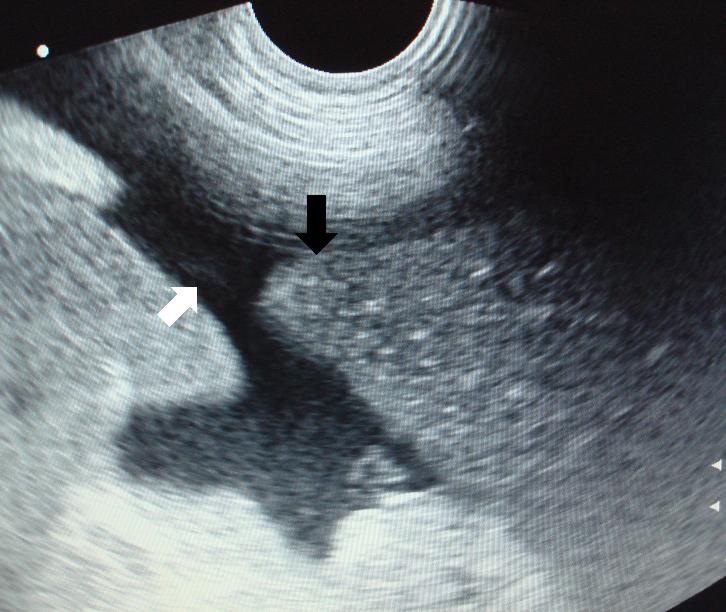

Po odsátí jsme opět sonograficky zkontrolovali srdce a osrdečník (černá šipka ukazuje na zbytek tekutiny, která v osrdečníkovém vaku po odsátí zůstala):

Echokardiografie-perikardiální efuze-stav po odsátí tekutiny